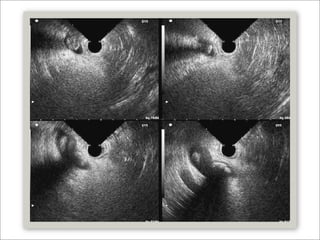

   Ultrasonido Endoscópico (EU)

   Sensibilidad y especificidad mayor al 95%